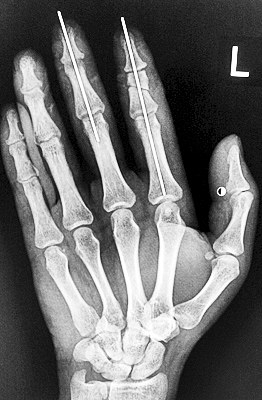

術(shù)后X光顯示,骨骼對位良好。

最終,盧微波和團(tuán)隊(duì)找好了需要的血管和神經(jīng),做好標(biāo)記后,開始固定食指骨骼、吻合肌腱,最后在顯微鏡下用直徑20微米的無創(chuàng)顯微縫合線開始吻合血管和神經(jīng)。

在經(jīng)過兩個(gè)多小時(shí)手術(shù)后,早上8時(shí)許,盧微波下令松止血帶,數(shù)十秒后男子蒼白的食指逐漸紅潤起來,食指在離體10個(gè)小時(shí)后恢復(fù)血運(yùn)。

緊接著,盧微波又開始中指再植手術(shù)。上午10時(shí)許,中指在離體12小時(shí)后也成功恢復(fù)血運(yùn)。